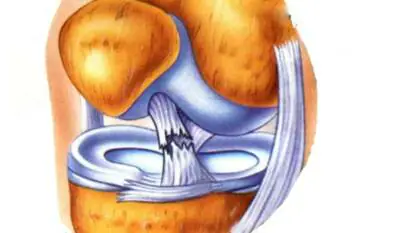

- Ligament and tendon tears

- Solid ligament fractures